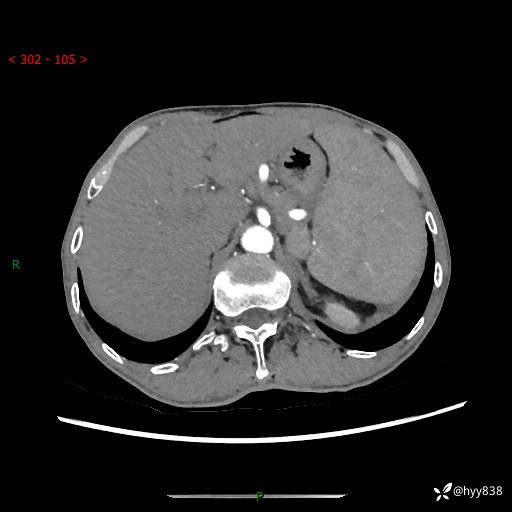

老年男性,脾大并脾脏弥漫粟粒状低密度,淋巴瘤 VS 肉芽肿 VS 血管瘤---结果公布

简要病史: 患者于3月前无明显诱因出现脾大,伴腹部轻微不适,具体不详,无腹痛、腹泻、腹胀,无头晕、头痛、乏力,无恶心、呕吐、呕血,无胸闷、气短、胸痛不适

上腹部CT平扫+增强